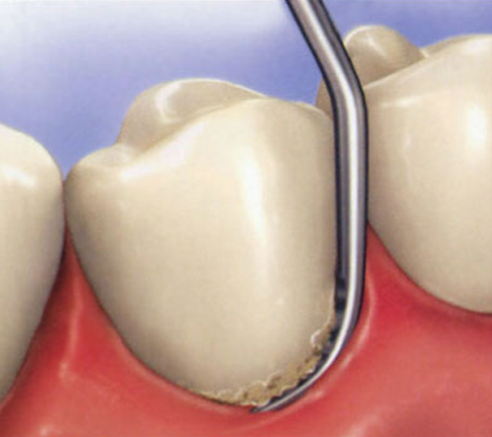

It was previously believed that periodontal disease was simply caused by bacteria that calcify, and that scraping off everything that could be seen or felt would lead to good health (Figure 1).1 But, as it turns out, that is not necessarily the case.

Fig. 1 Mechanical debridement, the traditional method of removing plaque and calculus.

Figure 1